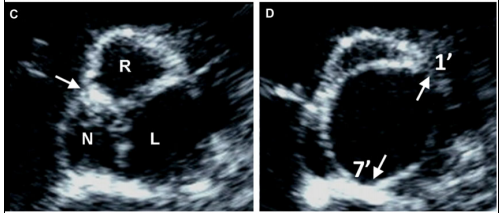

最新国际共识认为仅基于外科角度的Sievers分型仍有局限性,因此新的分型为:融合型、双窦型和部分融合型。其中融合型最常见,占90%~95%,相当于TypeⅠ型。双窦型BAV并不常见,占5%~7%,由大小、形状大致相同的两个瓣叶构成,分前侧对侧表型和前后表型(图b)。部分融合型的流行率尚不清楚,表现为典型的三叶瓣膜,但在连合底部可见<50%的瓣尖融合。至于Sievers分型中的Type Ⅱ型,共识认为称单叶瓣较为合适。

双窦型